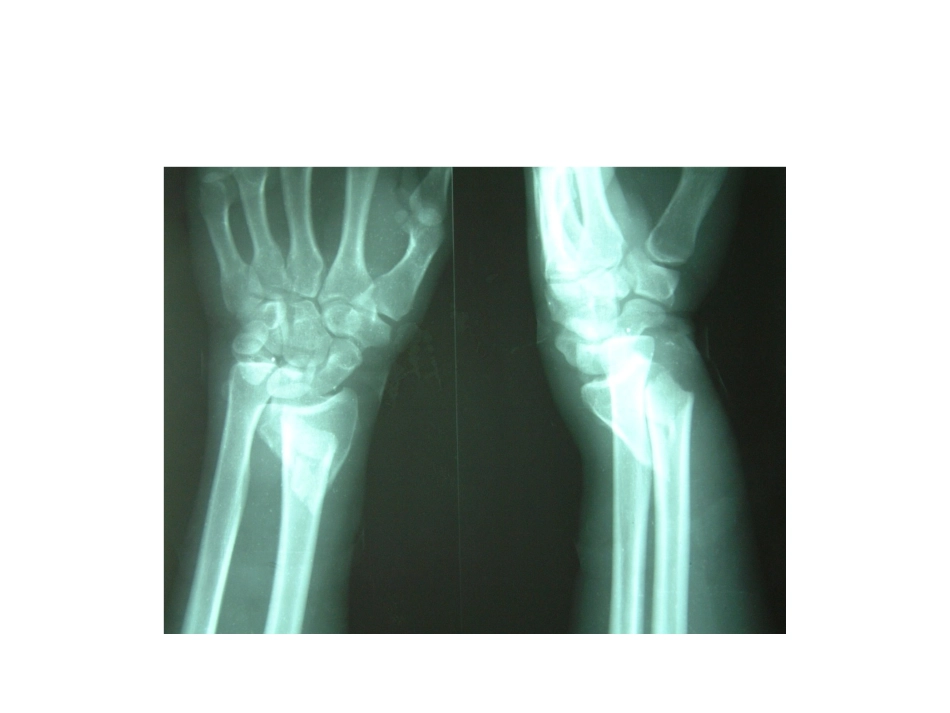

Colles骨折夹板外固定的优点李刚Colles骨折•桡骨下端骨折中的伸直型骨折,即侧面看呈“银叉”畸形,正面看呈“枪刺样”畸形,X线拍片可见骨折远端向桡、背侧移位,近端向掌侧移位,因此表现出典型的畸形体征。可同时伴有下尺桡关节脱位及尺骨茎突骨折。重要角度重要角度•掌侧倾斜角:桡骨远端与腕骨形成关节面,其背侧边缘长于掌侧,关节面向掌侧倾斜为10~15度。•尺侧倾斜角:桡骨下端外侧的茎突,较内侧长1.5CM,故其关节面向尺侧倾斜20~25度。手法整复的关键之一是恢复2个角度;关键之二是恢复桡骨的高度。小夹板外固定晋代葛洪的<<肘后救卒方>>中最早记载竹片固定骨折的治疗方法,是最早的文字记载。到隋唐时得到推广,孙思邈《千金要方》和王焘《外台秘要》都转载了葛洪的“用竹片夹裹之,勿令转动”和“重布夹裹”的固定技术。夹板外固定的原理:夹板固定是从肢体的生理功能出发,通过扎带对夹板的约束力,压垫对骨折断端防止或矫正成角畸形和侧方移位的效应力,充分利用肢体肌肉收缩活动时所产生的内在动力,使肢体内部动力因骨折所致的不平衡重新恢复到平衡。小夹板固定治疗colles骨折优点1、小夹板由于具有合理的构型和力学优势,具有保持骨折的相对稳定性,贯彻了功能活动的原则,能促进骨痂的形成,并使骨痂在功能状态下得到良好的塑形,这种治疗方法最根本的优点在于它体现的是“动静结合”和“弹性固定”的理念,这是它的精髓与灵魂所在。小夹板固定治疗colles骨折优点2、能根据受伤部位灵活选择小夹板的大小和长度,并有针对地进行塑形,可将患肢合理地固定在屈曲中立位,兼顾患指功能与有效固定。3、在用扎带固定夹板时,及时调节其松紧度,因弹性夹板内棉垫的缓冲和肌肉收缩活动时夹板与患指表面接触点压力的经常变化,大大减轻了夹板对皮肤的持续压迫,既可达到固定目的,又不会压坏皮肤和造成患指远端严重缺血。小夹板固定治疗colles骨折优点4、小夹板局部外固定治疗骨折,既能保持骨折端的稳定,又较少干扰骨折承受的应力状态,将肌肉收缩活动使骨折移位的消极因素转变为维持固定、矫正残余畸形、加速骨折愈合的积极因素。小夹板固定治疗colles骨折优点5、小夹板质轻,可与患指形成一个整体,不切开剥离骨膜,不影响骨折部的血运,有效减少了骨折不愈合和迟缓愈合,不损伤关节面,利于关节功能恢复。小夹板固定手部骨折取材方便、制作简单、设计合理、功能恢复快,病人痛苦少而乐于接受。小夹板固定治疗colles骨折优点结语小夹板外固定是治疗Colles骨折的一种简便、有效、可靠的方法,具有诸多优点,临床效果满意。